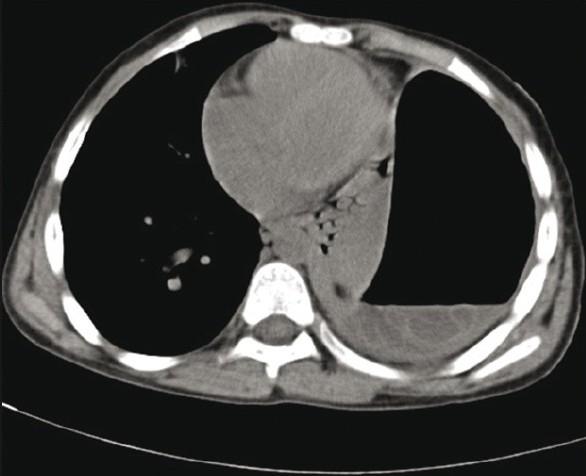

Joshi Jyotsna M

Department of Respiratory Medicine, T. N. Medical College and B. Y. L. Nair Hospital, Mumbai, India.

Lung India. 2011 Oct;28(4):315-6. doi: 10.4103/0970-2113.85745.